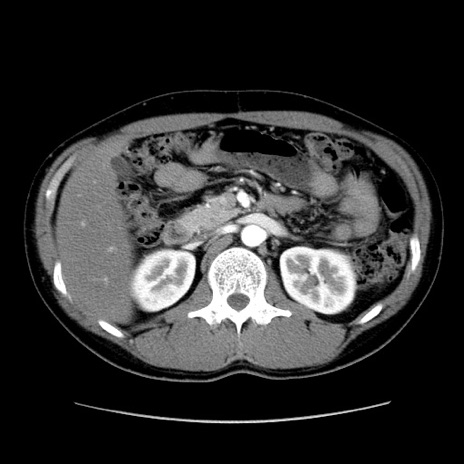

症例36(横断像)

【症例】20歳代 男性

【主訴】心窩部痛

【現病歴】今朝より上腹部痛あり。一旦軽快していたが再度出現したため救急要請。昨日夕に白身の魚を含む刺身を食べた。

【身体所見】BP 136/89mmHg、HR 74/min、BT 37.0℃、腹部:膨満、軟、心窩部に圧痛あり。反跳痛なし、筋性防御なし、腸雑音やや亢進あり。

【データ】WBC 17700、CRP 0.48